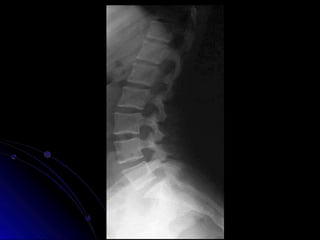

AP Columna Lumbar

Estructuras Visualizadas

•Cuerpos vertebrales L1-L5

•Pediculos

•PE's

•Lamina

•PT's

•Base Sacral

•Sombra del Psoas

AP Columna Lumbar -

Marcado

LUMBAR LATERAL -